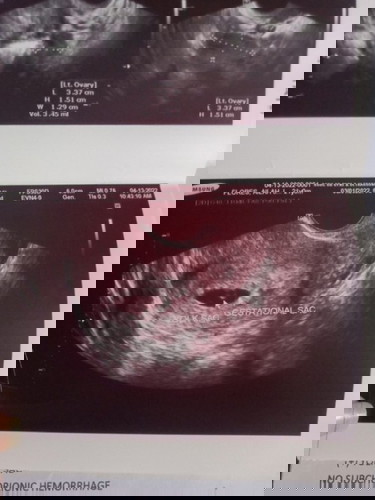

6weeks pregnant sac palang nakita. UPDATE! MAY BABY NAPO AND HEARTBEAT 10WEEKS PREGGY HERE

Hello mommies? Nagpa transv po ako kanina sad to say yolk and gestational sac lang po nakita. Normal po ba yun? Pinapabalik ako after 2weeks. Possible pa kaya magka embryo? Sobrang worried po ako. Sino napo nakaranas neto? Share naman po ng experience niyo. Nagbrown discharge dn ako nung isng araw e.#1stimemom#advicepls #worryingmom

Magbasa pasame po tayo. nung 6 weeks po ako sac lang po at yolk. sabi pa ng first ultrasound ko possible for ectopic pa kasi sobrang sakit niya sa left side. pinabalik ako 2 weeks after, ika 7 weeks and 3 days ko na non, may nakita ng embryo at heartbeat. sobrang happy ko at ng ob ko. pray ka lang po always.